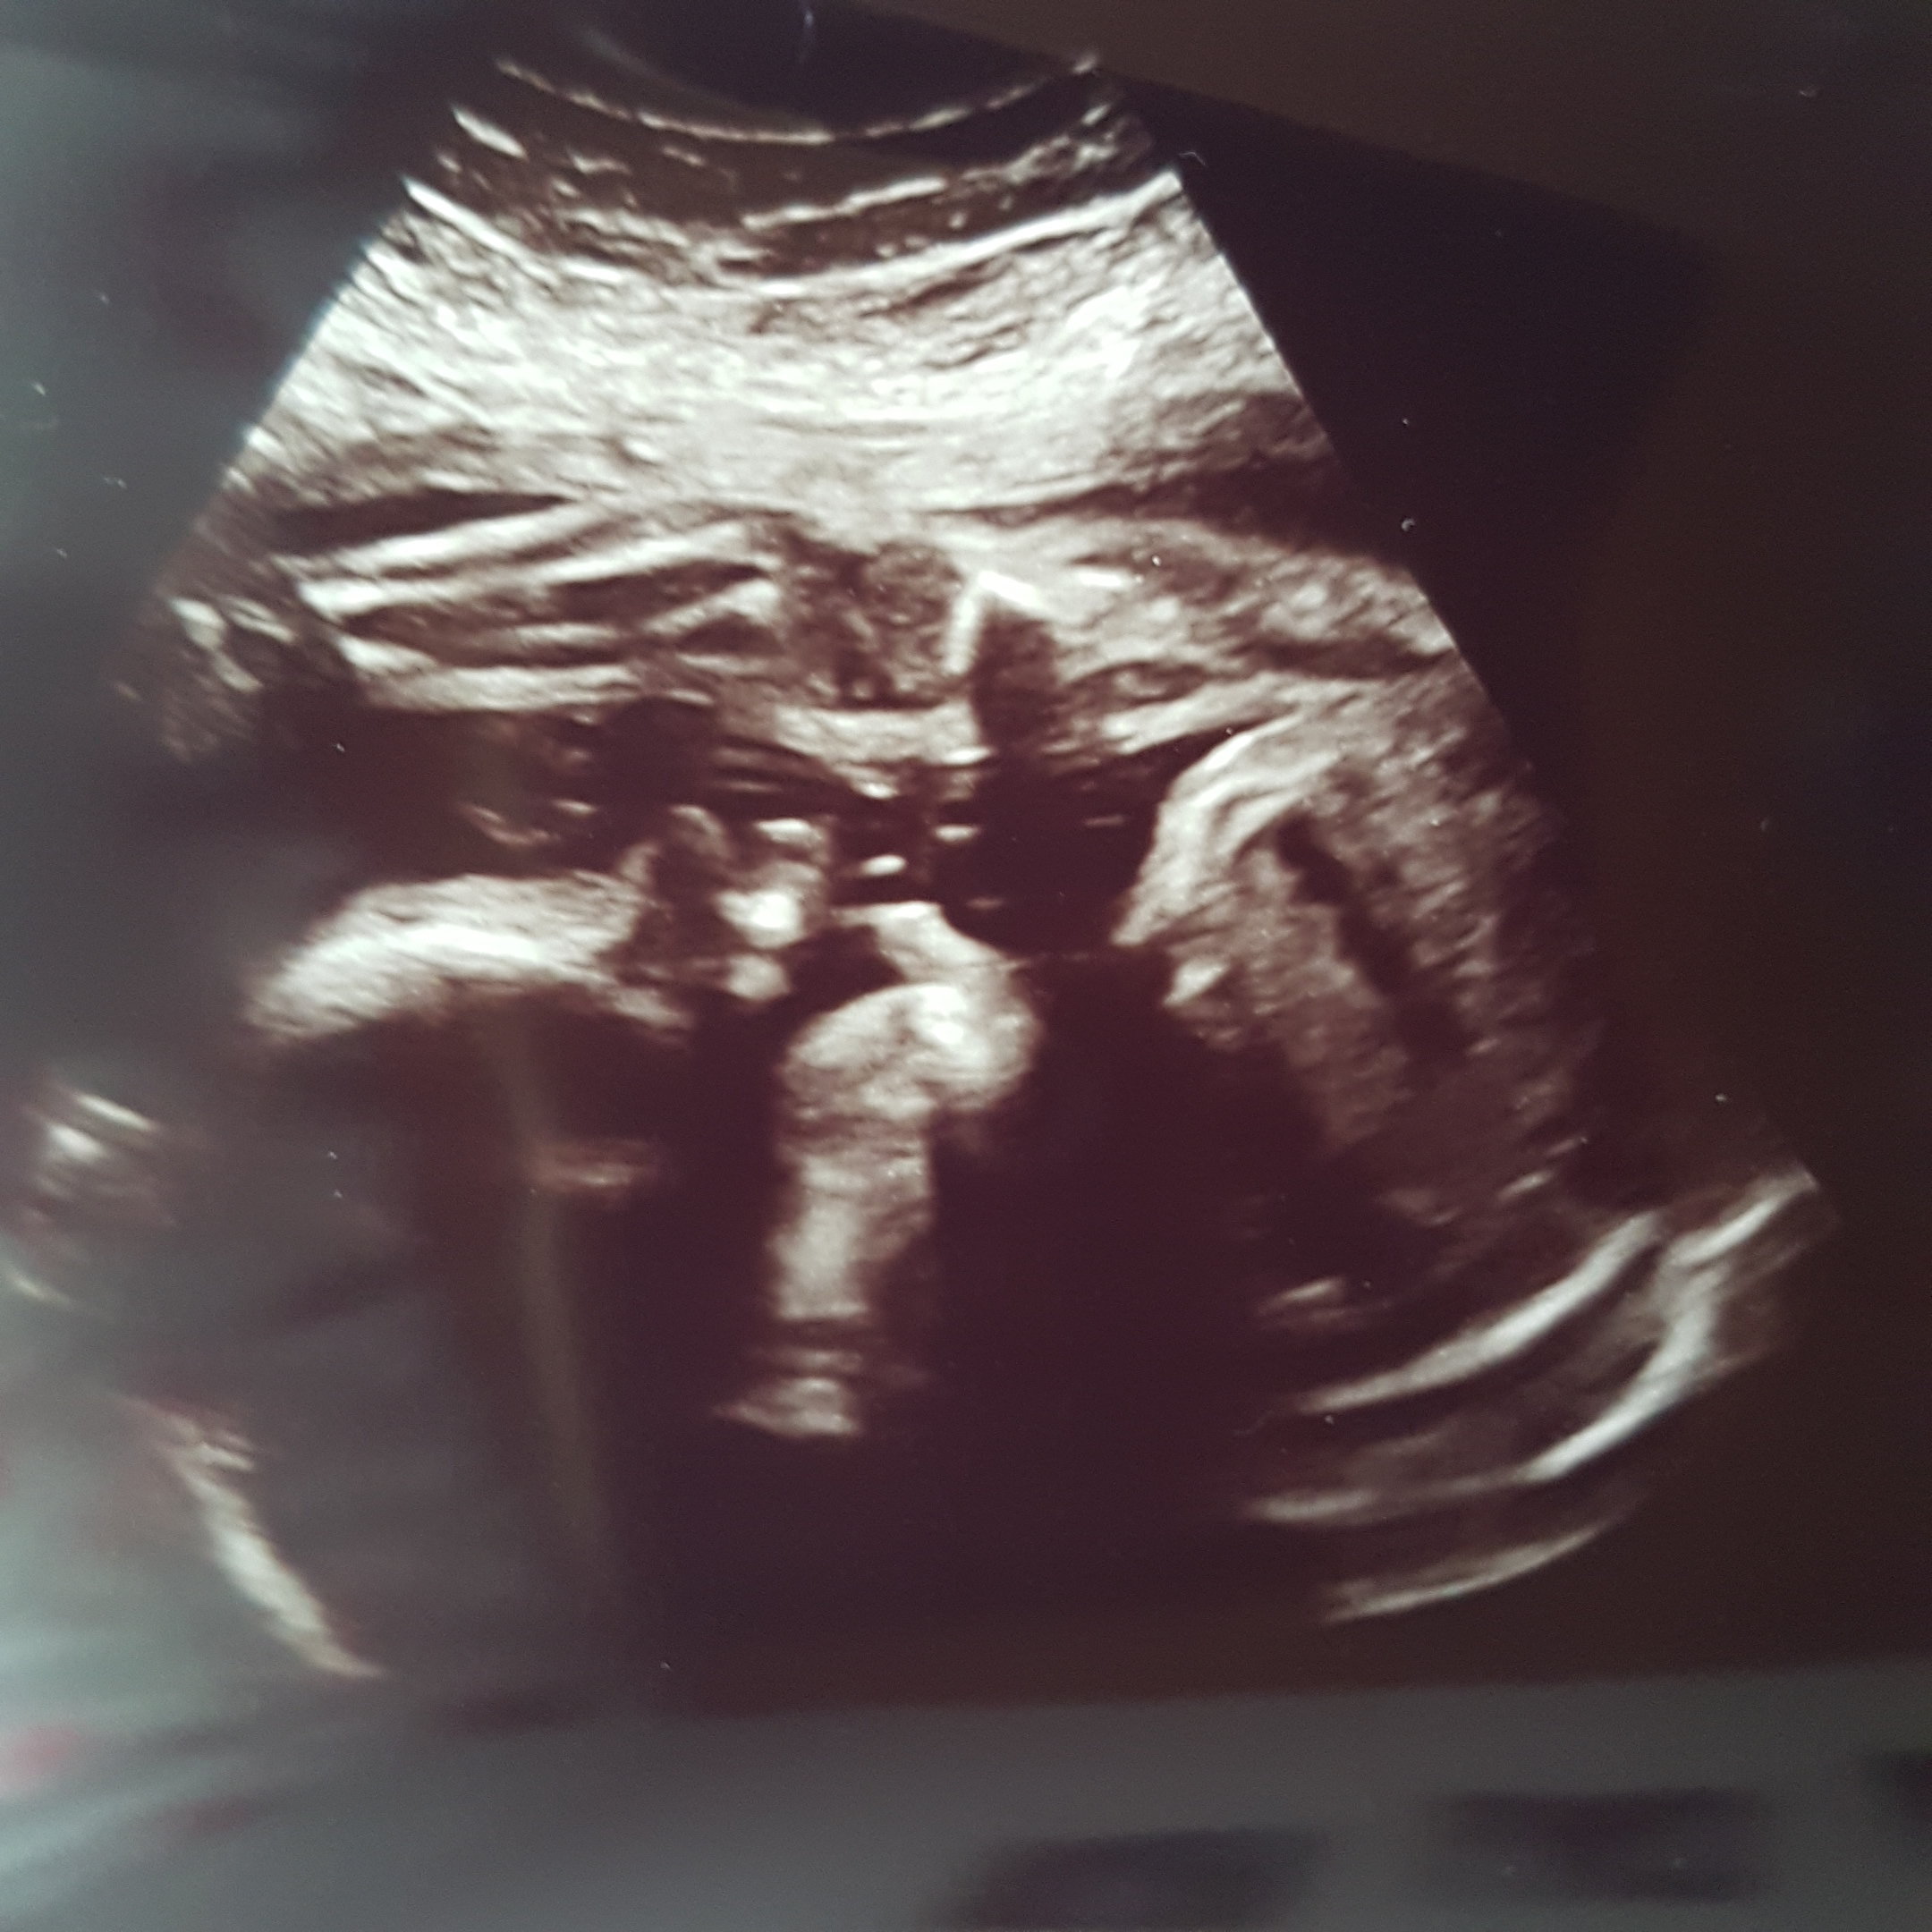

Hej. Jesteśmy już po wizycie. U mnie plus 3kg , żelazo poszło w górę co mnie cieszy. Dzisiaj 26+1 synuś waży 971g miałam robione ktg serduszko bije jak dzwon.

Lekarz się śmiał że mały akrobata rośnie,bo nóżki ma przez buźka.

15046038300831790369707.jpg 1504603854598927545536.jpg

Załączniki

• 15046038300831790369707.jpg

15046038300831790369707.jpg

453,1 KB · Wyświetleń: 170

• 1504603854598927545536.jpg

1504603854598927545536.jpg

465,7 KB · Wyświetleń: 183